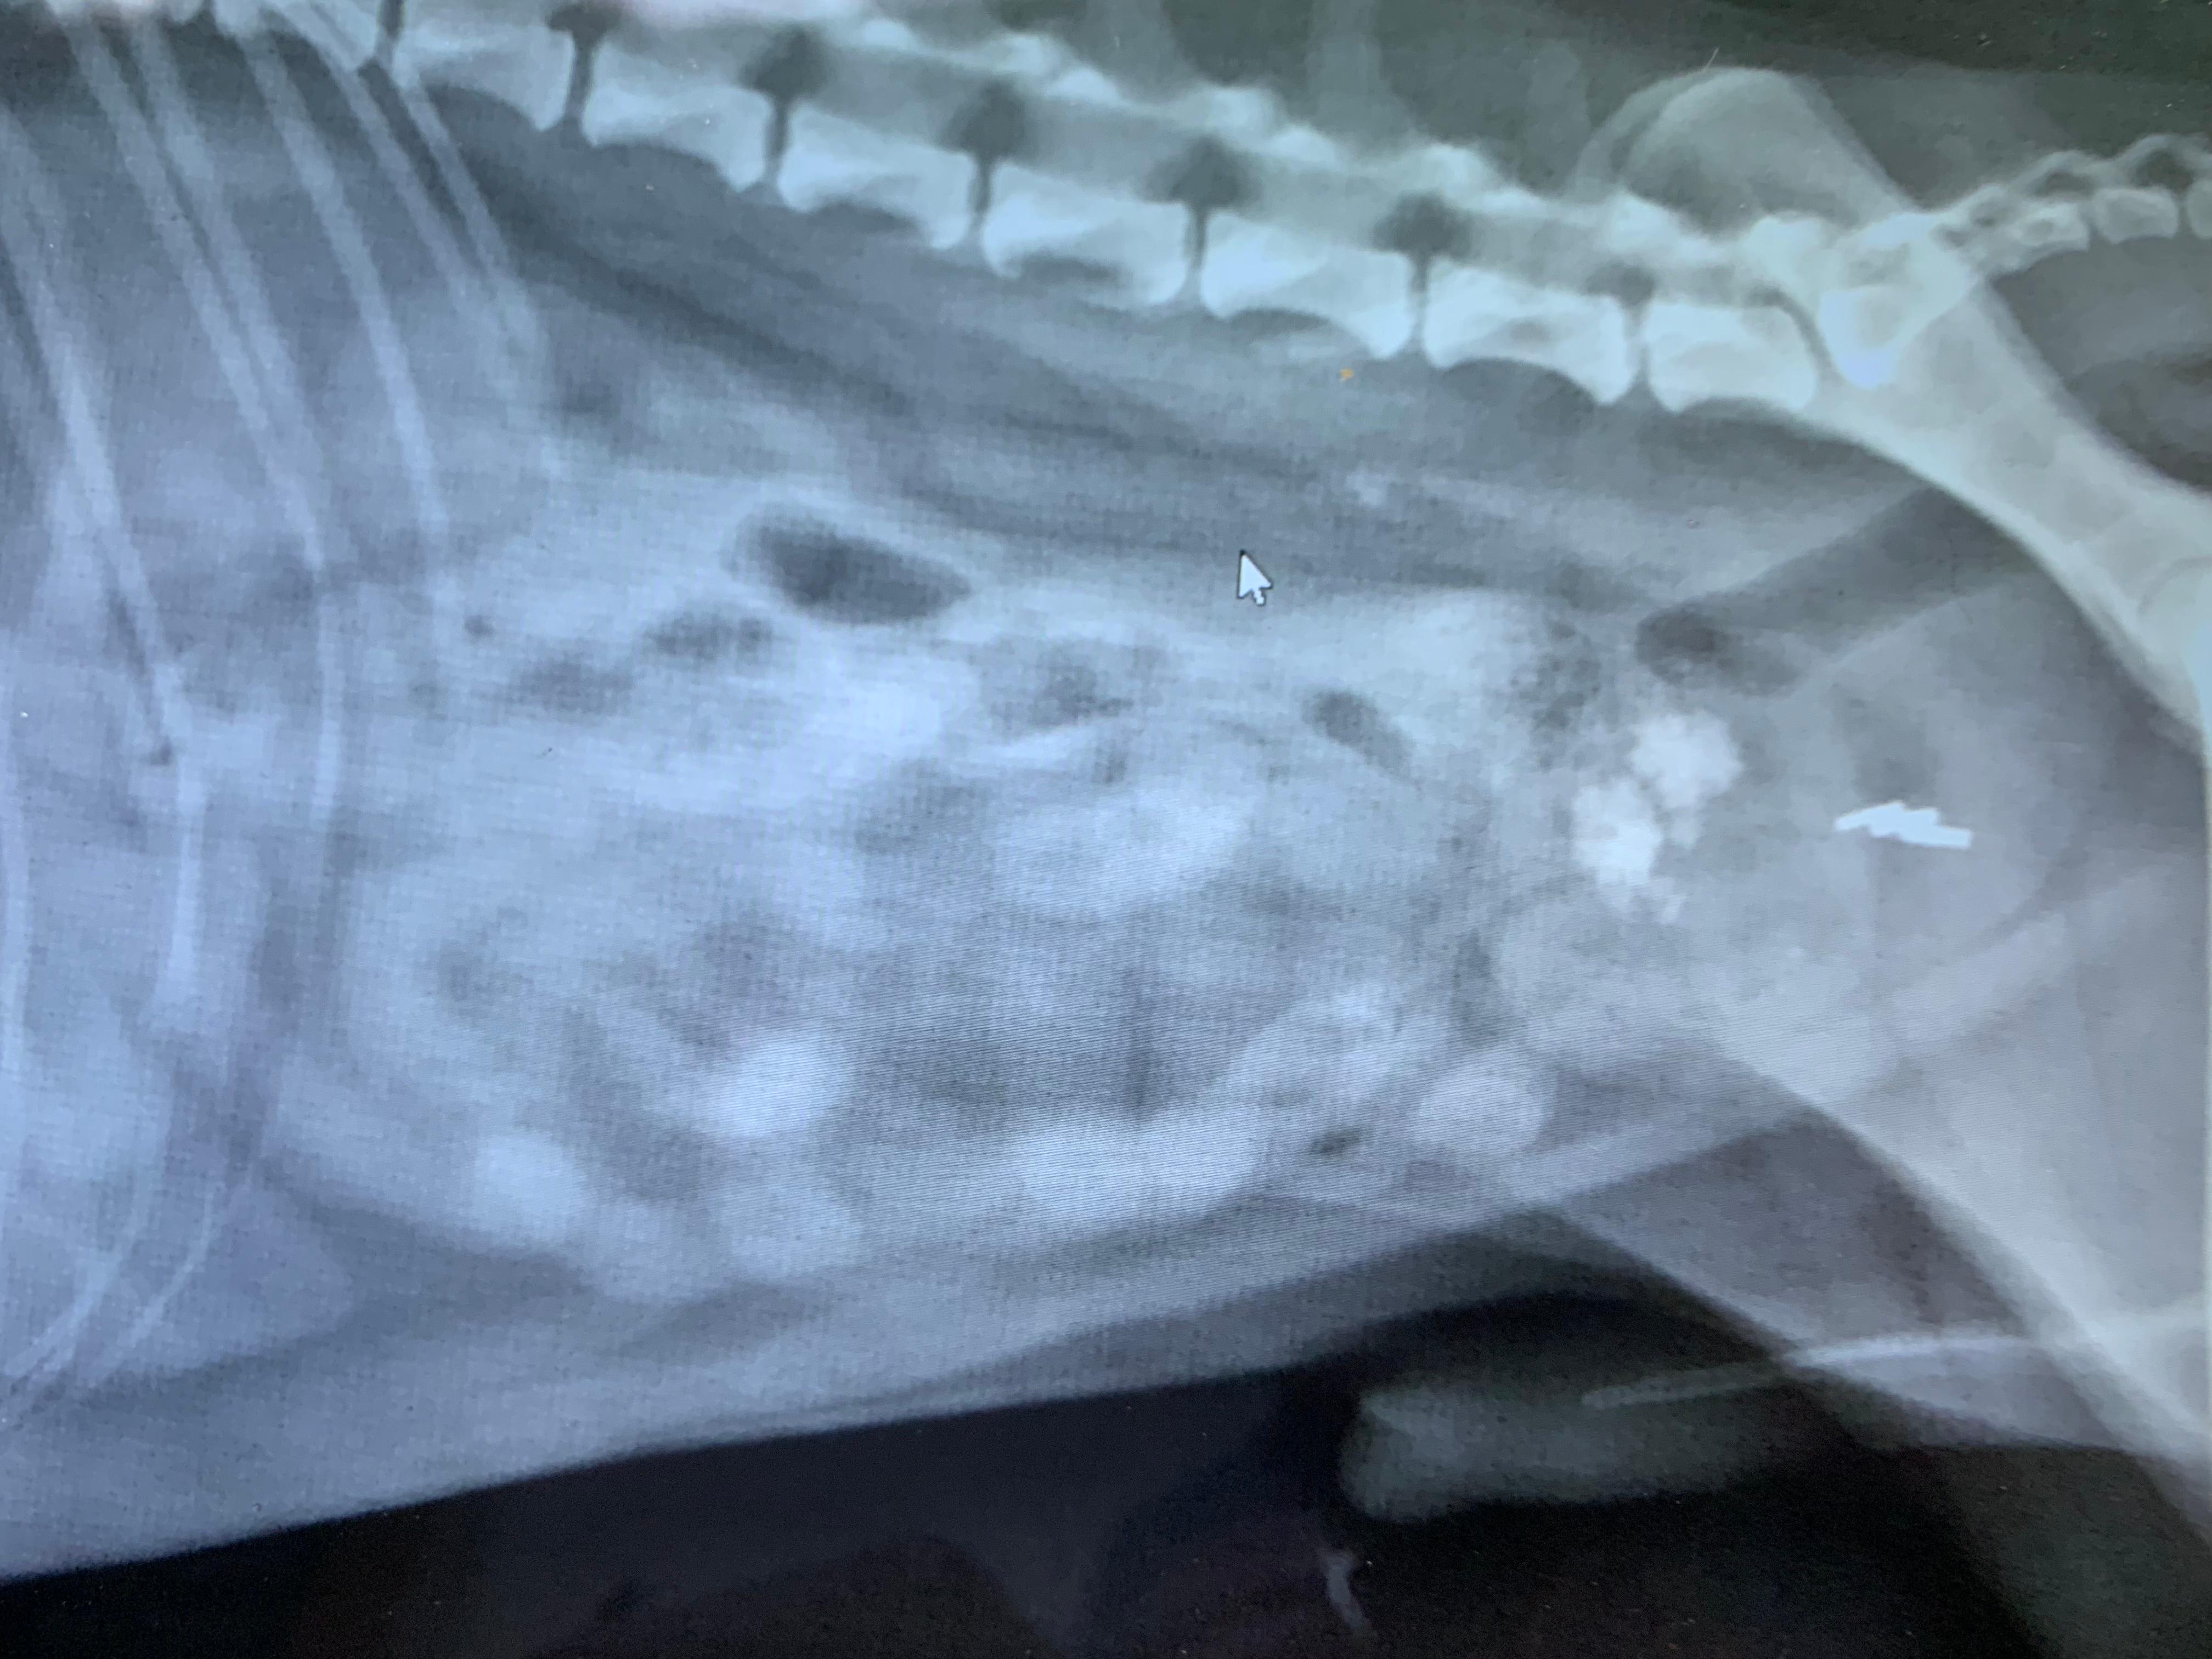

Our 7 year old jack russel-Pomeranian mix was diagnosed today to have kidney stones. We were sent home with a new diet and a lot of worry. Should I go get a second opinion?

I agree that it looks like Buddy has bladder and urethral stones. A diet might help to dissolve them, although the stones in his urethra are a bit more concerning and may not dissolve. He is at risk for urethral obstruction at any time which would be an emergency. Surgery to remove the stones might be another option. If you feel like you want a second opinion you certainly could make an appointment with another vet, or you could ask about referral to an internal medicine specialist.